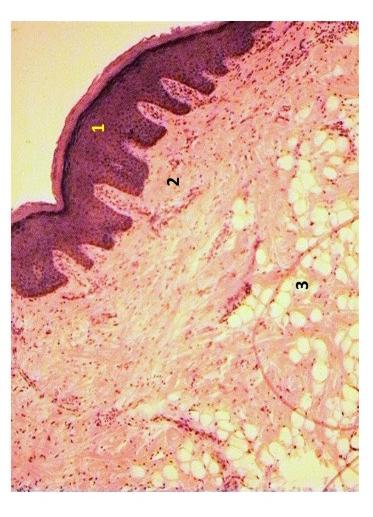

Поверхность слизистой оболочки небной миндалины с поверхностно расположенным многослойным плоским, а у основания - призматическим эпителием - 1, подслизистая основа - 2, которая формирует соединительнотканную капсулу миндалины . Гистологический срез небной миндалины при соотношении апоптоз/некроз в лимфоцитах гомогената 2,53 .